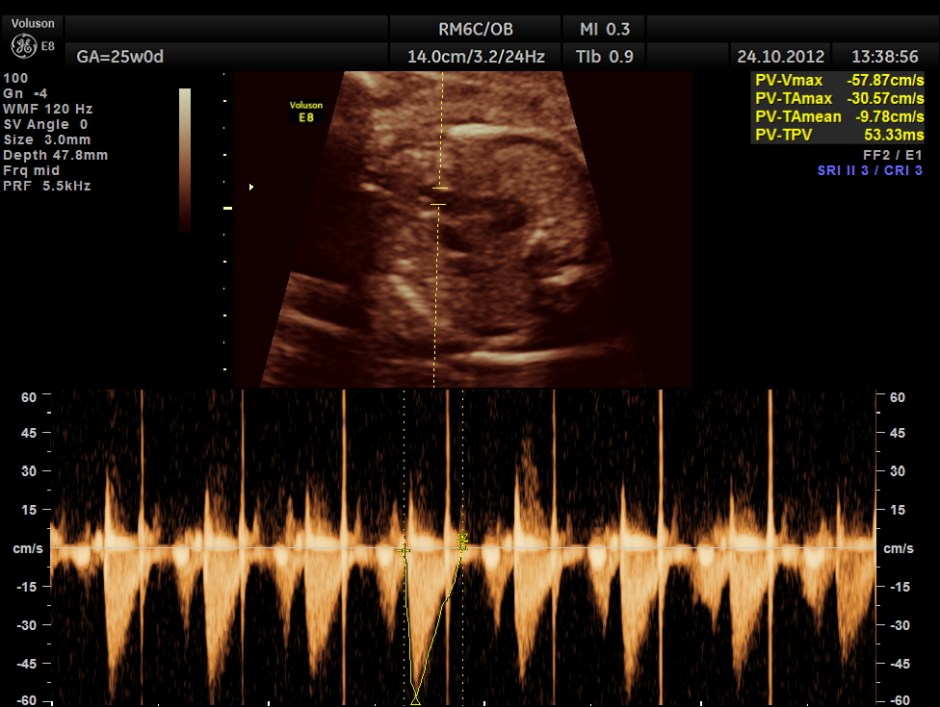

Spectral doppler shows high velocity flow across the defect